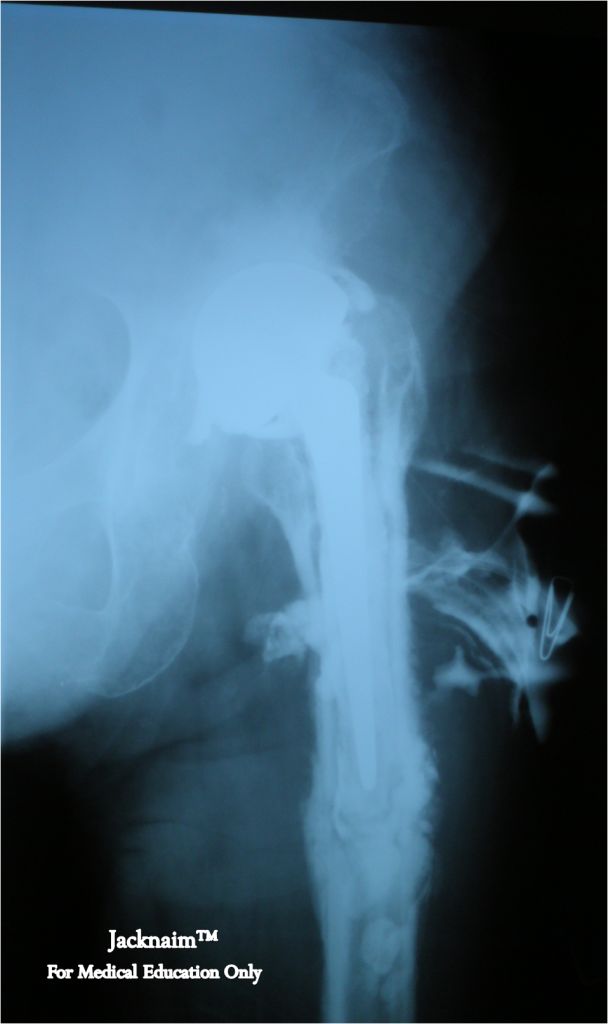

An 80 years old lady with history of bipolar implants of the left leg for 2 years due to fracture of the neck of femur and defaulted follow up presented with left leg pain and chronic serous discharge from the implant site. Below is the radiological image of his left femur.

1) Describe the radiological findings

2) What is your provisional diagnosis